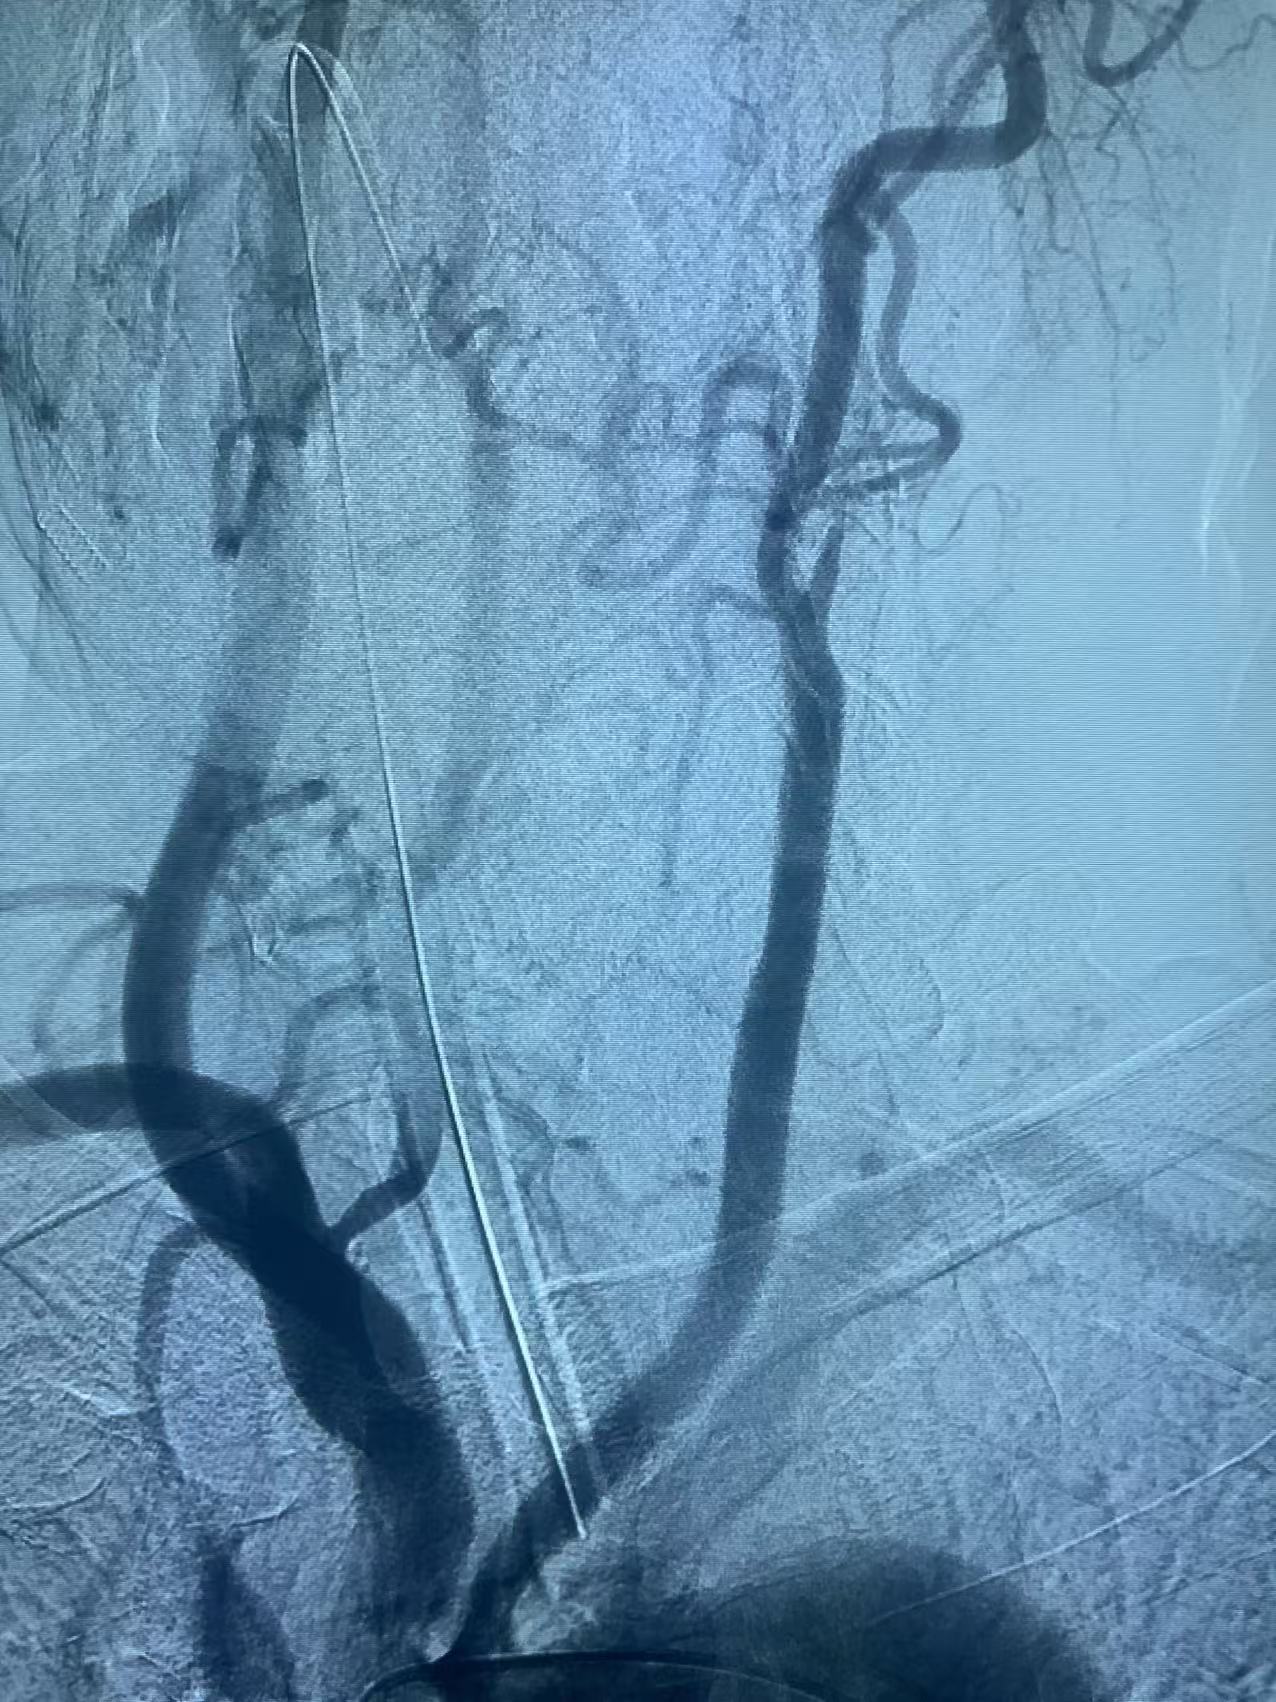

颈内动脉开口重度狭窄基础之上的急性闭塞